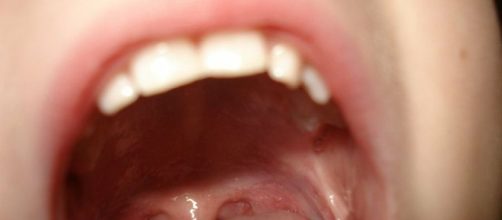

Las aftas bucales son úlceras pequeñas o heridas cubiertas por una membrana blanca que salen dentro de la boca, puede salir una o varias muy pequeñas al mismo tiempo en la boca de una persona, una de sus causas pueden ser infecciones por falta de limpieza bucal.

La falta de hierro o pérdida de este mineral también causa debilidad en la mucosa que luego da origen a la aparición de aftas. Cuando una persona se muerde la boca es normal que aparezca un afta pero lo normal es que desaparezca en 3 o 4 días, cuando eso no es así y tarda más tiempo quiere decir que la mucosa no se está regenerando bien y puede tardar en sanar hasta por dos largas semanas.

Las aftas bucales no son contagiosas como algunos piensan, así que durante un beso la otra persona no correrá ningún riesgo, si las aftas se repiten constantemente es recomendable asistir al médico ya que no es normal que eso ocurra y quizás las causas de su aparición sean aún más serias.